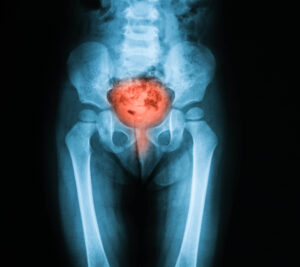

Understanding Bladder Cancer: Signs, Risks, and When to Seek Help

Bladder cancer is one of the most common cancers in the United States, particularly affecting older adults and more frequently diagnosed in men than women. As with many cancers, early detection can significantly improve outcomes, which makes awareness of symptoms and risk factors critically important.